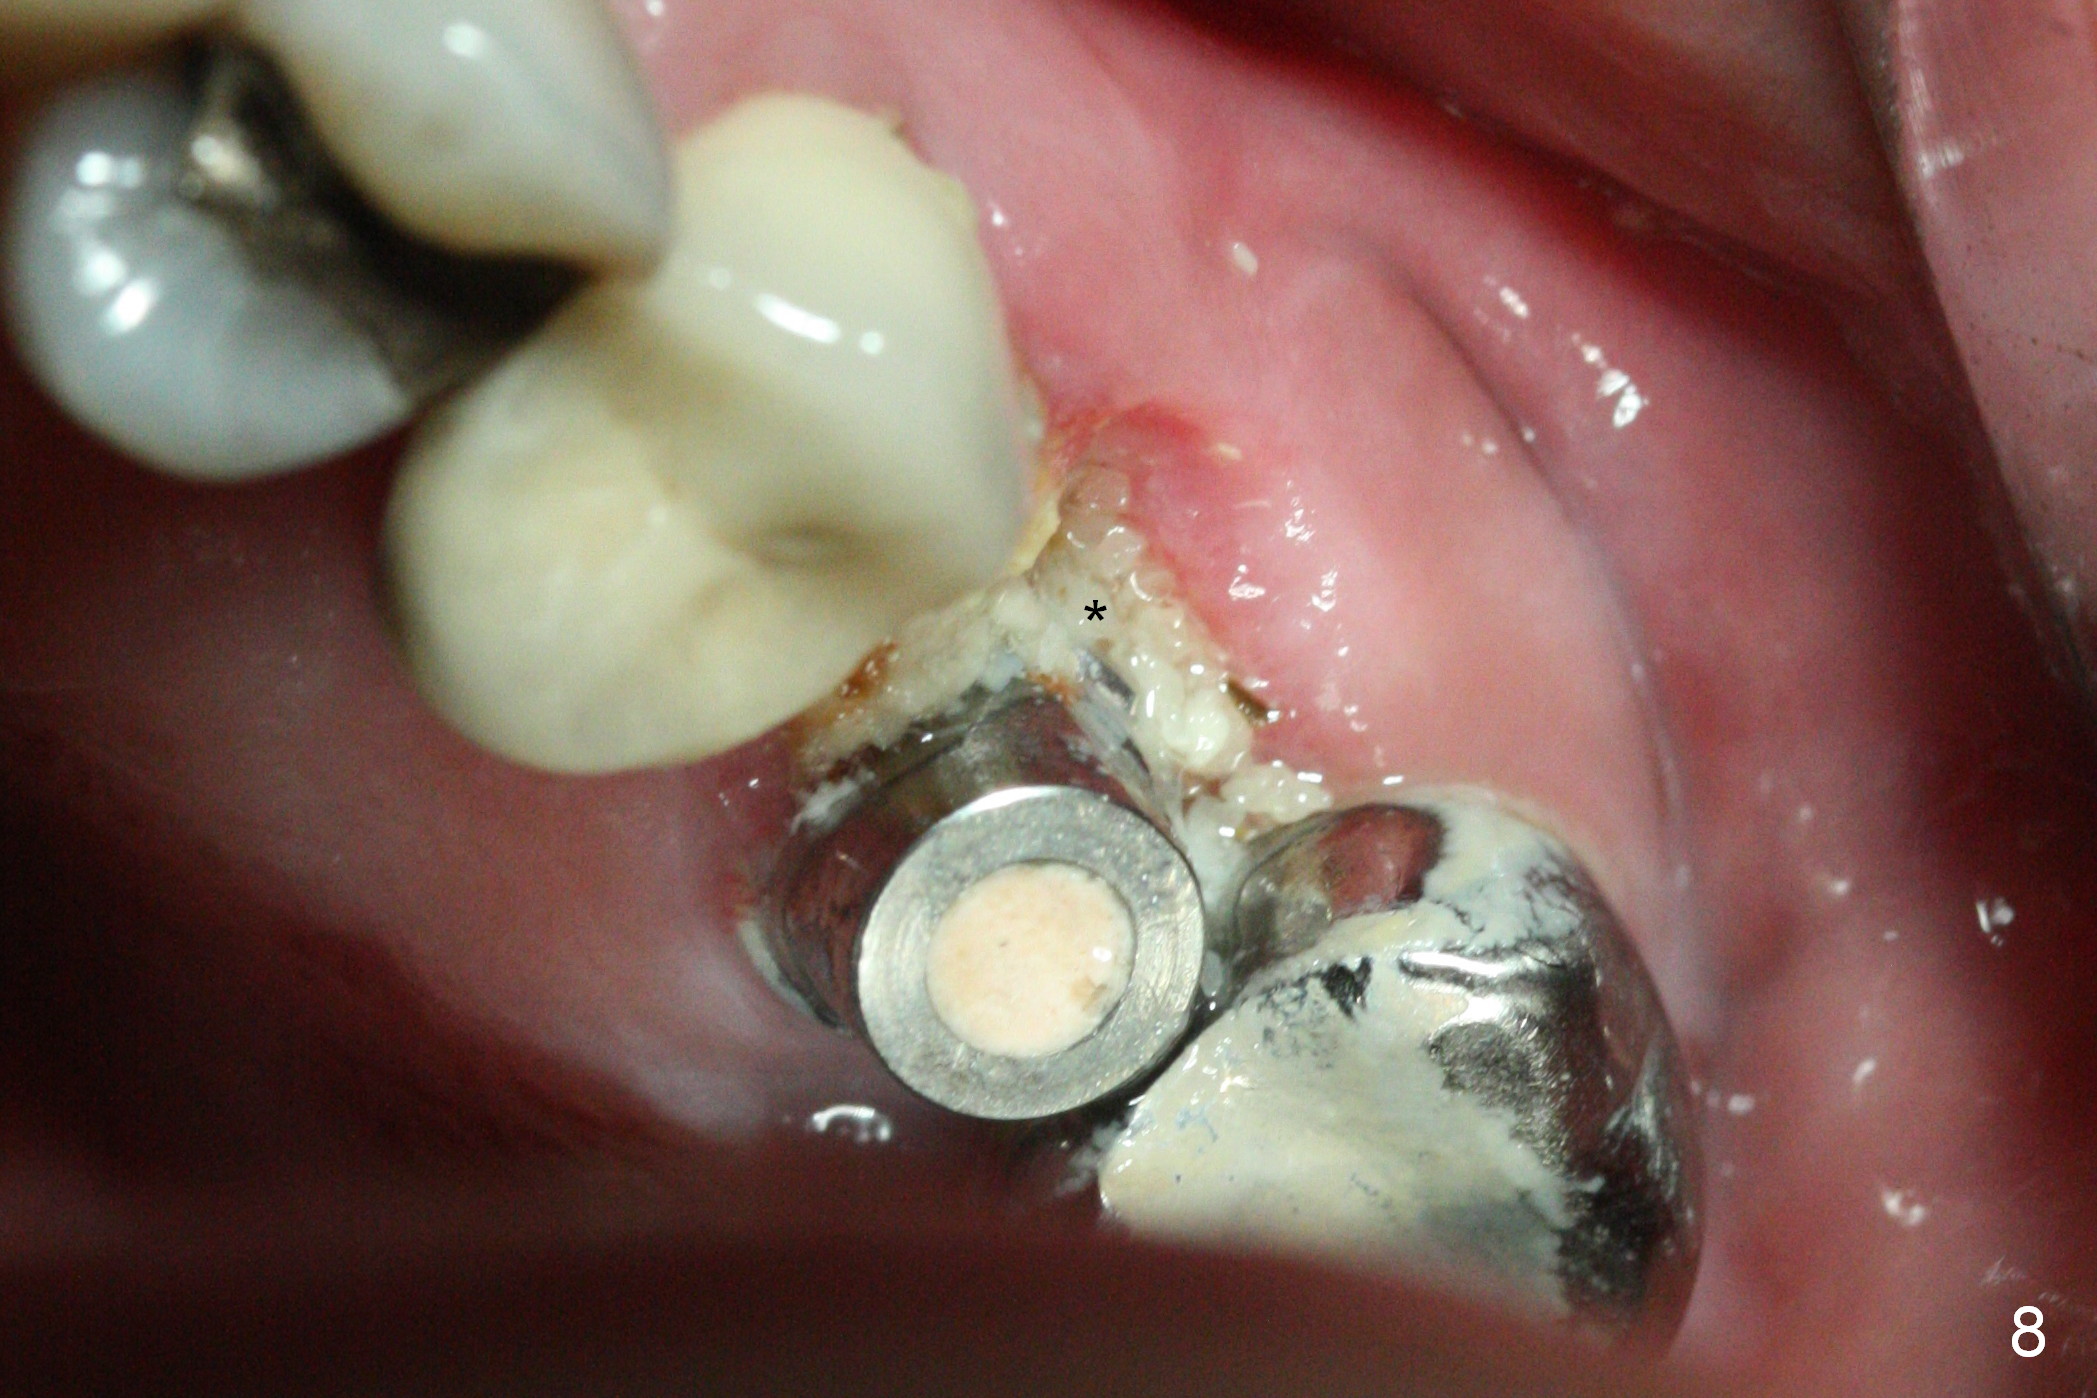

The patient is doing well 9 days postop.  The immediate provisional is loose and over-sized.  It is removed for trimming and reline; the socket and bone graft (Fig.8 *) are healing.  It appears that an angled abutment is required next time of provisional revision.  When an angled abutment is being placed 23 days postop (Fig.9), it appears to wiggle the implant due to its long leverage.  Instead a healing abutment is placed.  The implant is unstable 4.5 months postop with seemingly excessive bone-implant gap (Fig.10 <).  The 5.5x9 mm implant is removed.  A 5x17 mm tap is used to change the trajectory and sinus lift, followed by 6x17 one (Fig.11).  Finally a 6x14 mm tissue-level implant is placed with insertion torque > 50 Ncm (Fig.12; vs. <20 Ncm (Fig.7,10)) and improved trajectory.  An immediate provisional is fabricated to prevent the mesial drifting of the tooth #15 (Fig.13 P (*: occlusal clearance)).  By using the taps and placing the longer implant, the sinus lift is more obvious (compare Fig.10 and 12 (*)).  Sinus lift remains evident 3.5 months postop (Fig.14) with apparently osteointegration (Fig.15).